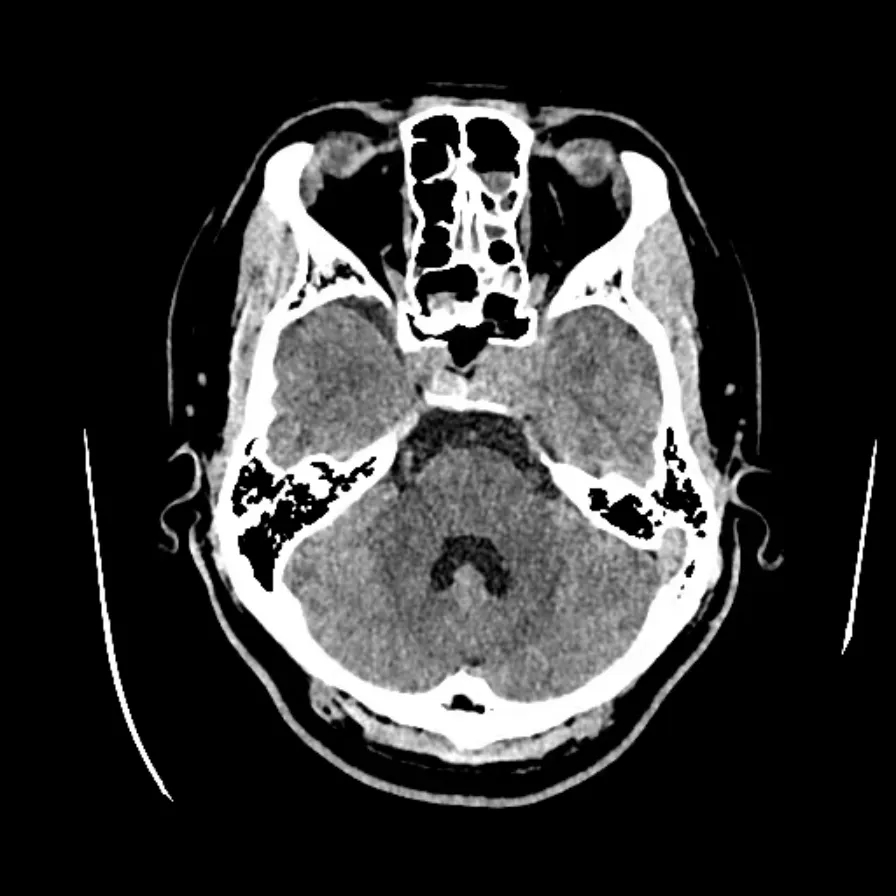

患者小王(化名)今年19岁,1年前出现视力下降,起初以为是最近玩手机游戏太多导致的,因此并没有太在意。直到两个月前,小王还发现自己眼睛看东西的范围越来越小,仅能看到自己鼻子附近的范围,眼睛外侧全都看不到。这不仅仅是视力下降那么简单了,日常的生活都受到了严重的影响,小王在家人的陪同下在当地医院眼科就诊,刚开始以眼病进行诊治,经过眼科一系列的检查无果后行颅脑CT后才发现鞍区有占位性病变。“居然不是眼睛的问题,病根在脑子里?”这下家人都着急了,小王还很年轻,学业还未完成,赶紧来到西安医学院第一附属医院脑科医院神经外一科门诊,接诊医生为小张行颅脑MRI检查后发现其鞍内及鞍上存在垂体腺瘤,肿瘤直径已经超过3cm,属于巨大垂体瘤。由于肿瘤不断向上生长压迫视神经,导致双眼视力下降、双颞侧偏盲,已严重影响日常生活,如果进一步发展将导致双眼失明,手术已迫在眉睫。

面对患者年轻、肿瘤体积巨大、位置深、毗邻重要血管神经的复杂情况,西安医学院第一附属医院脑科医院院长刘卫平、神经外一科主任丁志斌团队经过充分术前评估,决定采用“神经导航辅助神经内镜下经鼻-蝶微创手术”。该手术无需开颅,借助鼻腔自然通道,在神经导航精准定位和神经内镜高清视野下切除肿瘤,具有创伤小、恢复快、并发症少等优势。